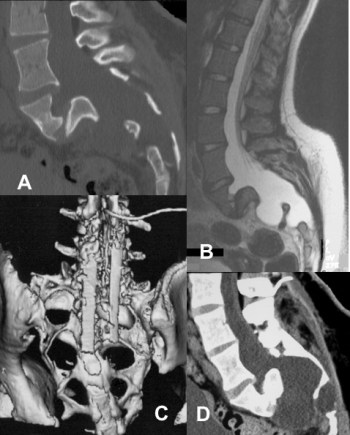

ci-contre : méningocèle avec lyse osseuse et spondyloptose (A, B), traitée par greffe postérieure et drainage kyste-péritonéal (C, D). du fait de l’absence de résistance des tissus (os et dure-mère) et de la combinaison à des neurofibromes extensifs, ils peuvent entrainer une déstabilisation rachidienne et pelvienne, nécessitant une stabilisation (greffe) protégée par un drainage lombaire comme ci-dessous.